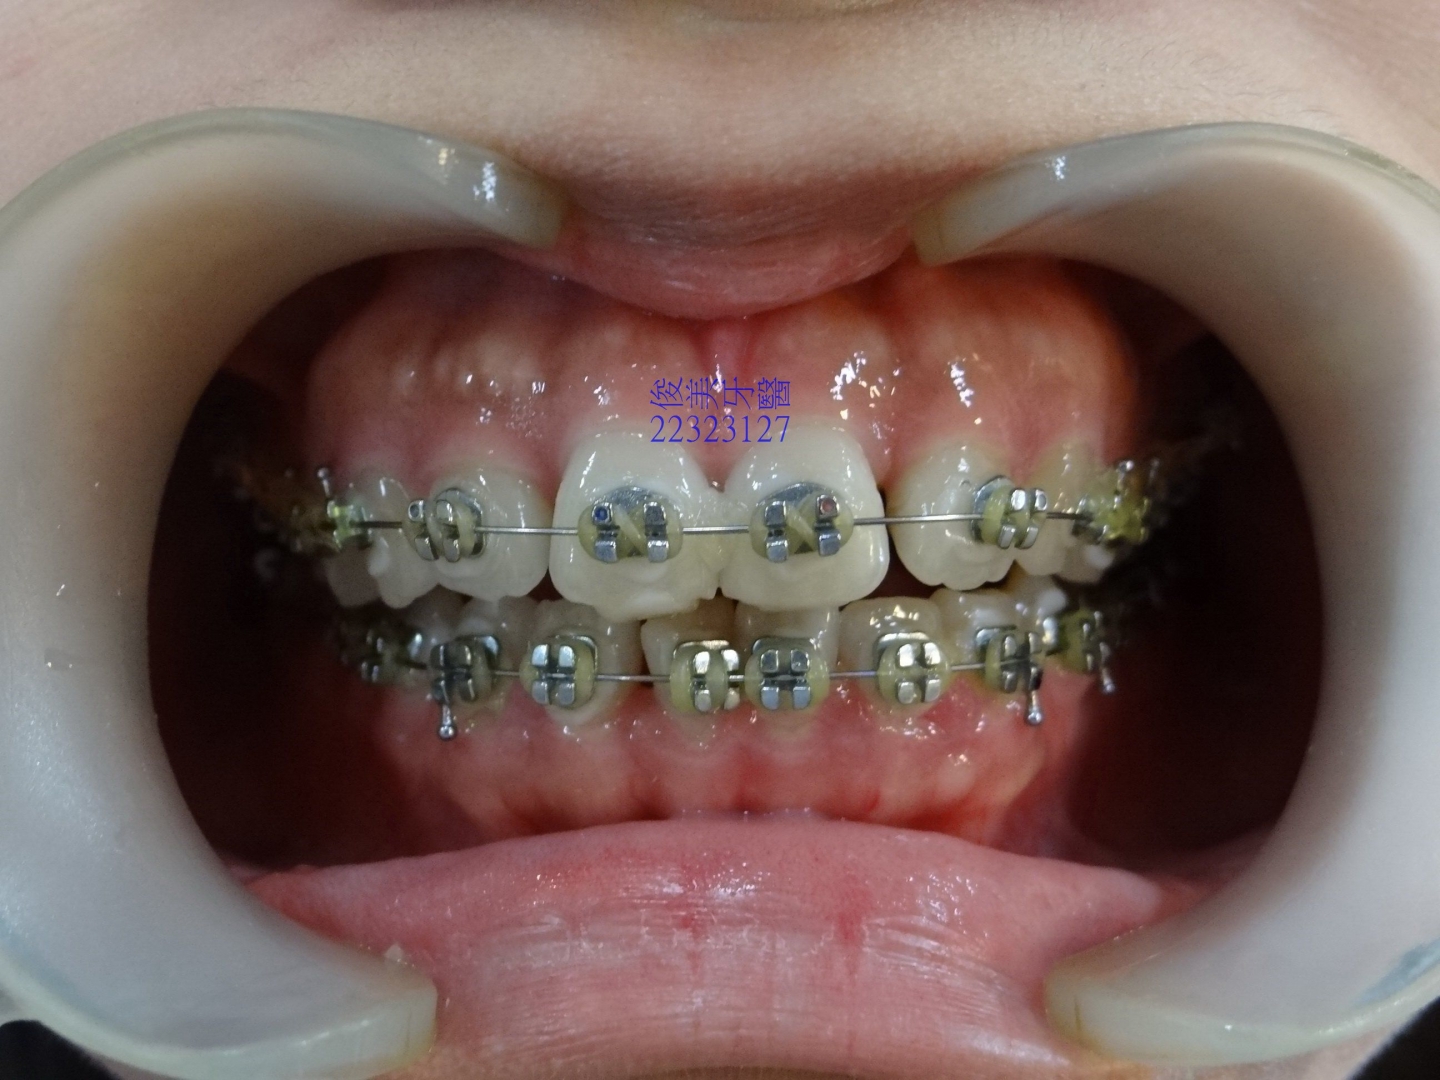

![]() 患者於門診中表示,牙齒很擁擠,想要改善;經醫師門診後,建議患者進行矯正治療即可改善。 ![]() 牙齒重疊... ![]() 有深咬現象... ![]() 上顎狀況... ![]() 下顎狀況... ![]() 左側咬合,牙齒往舌側傾斜...... . ![]() 右側咬合,牙齒往舌側傾斜...... ![]() 治療中....擁擠和深咬已改善.... ![]() 牙齒往後移.....將牙齒齒軸回正一點。 ![]() 治療結束,拆除矯正器了............. ![]() 患者好開心......牙齒整齊後,笑容更可愛了。 ![]() 也沒有暴牙的狀況。 ![]() 上顎牙弓狀況。 ![]() 下顎牙弓狀況。 ![]() 右側咬合狀況。 ![]() 左側咬合狀況。 ![]() 已拆除超過5年,依舊配戴維持器,保持最佳狀態。 |